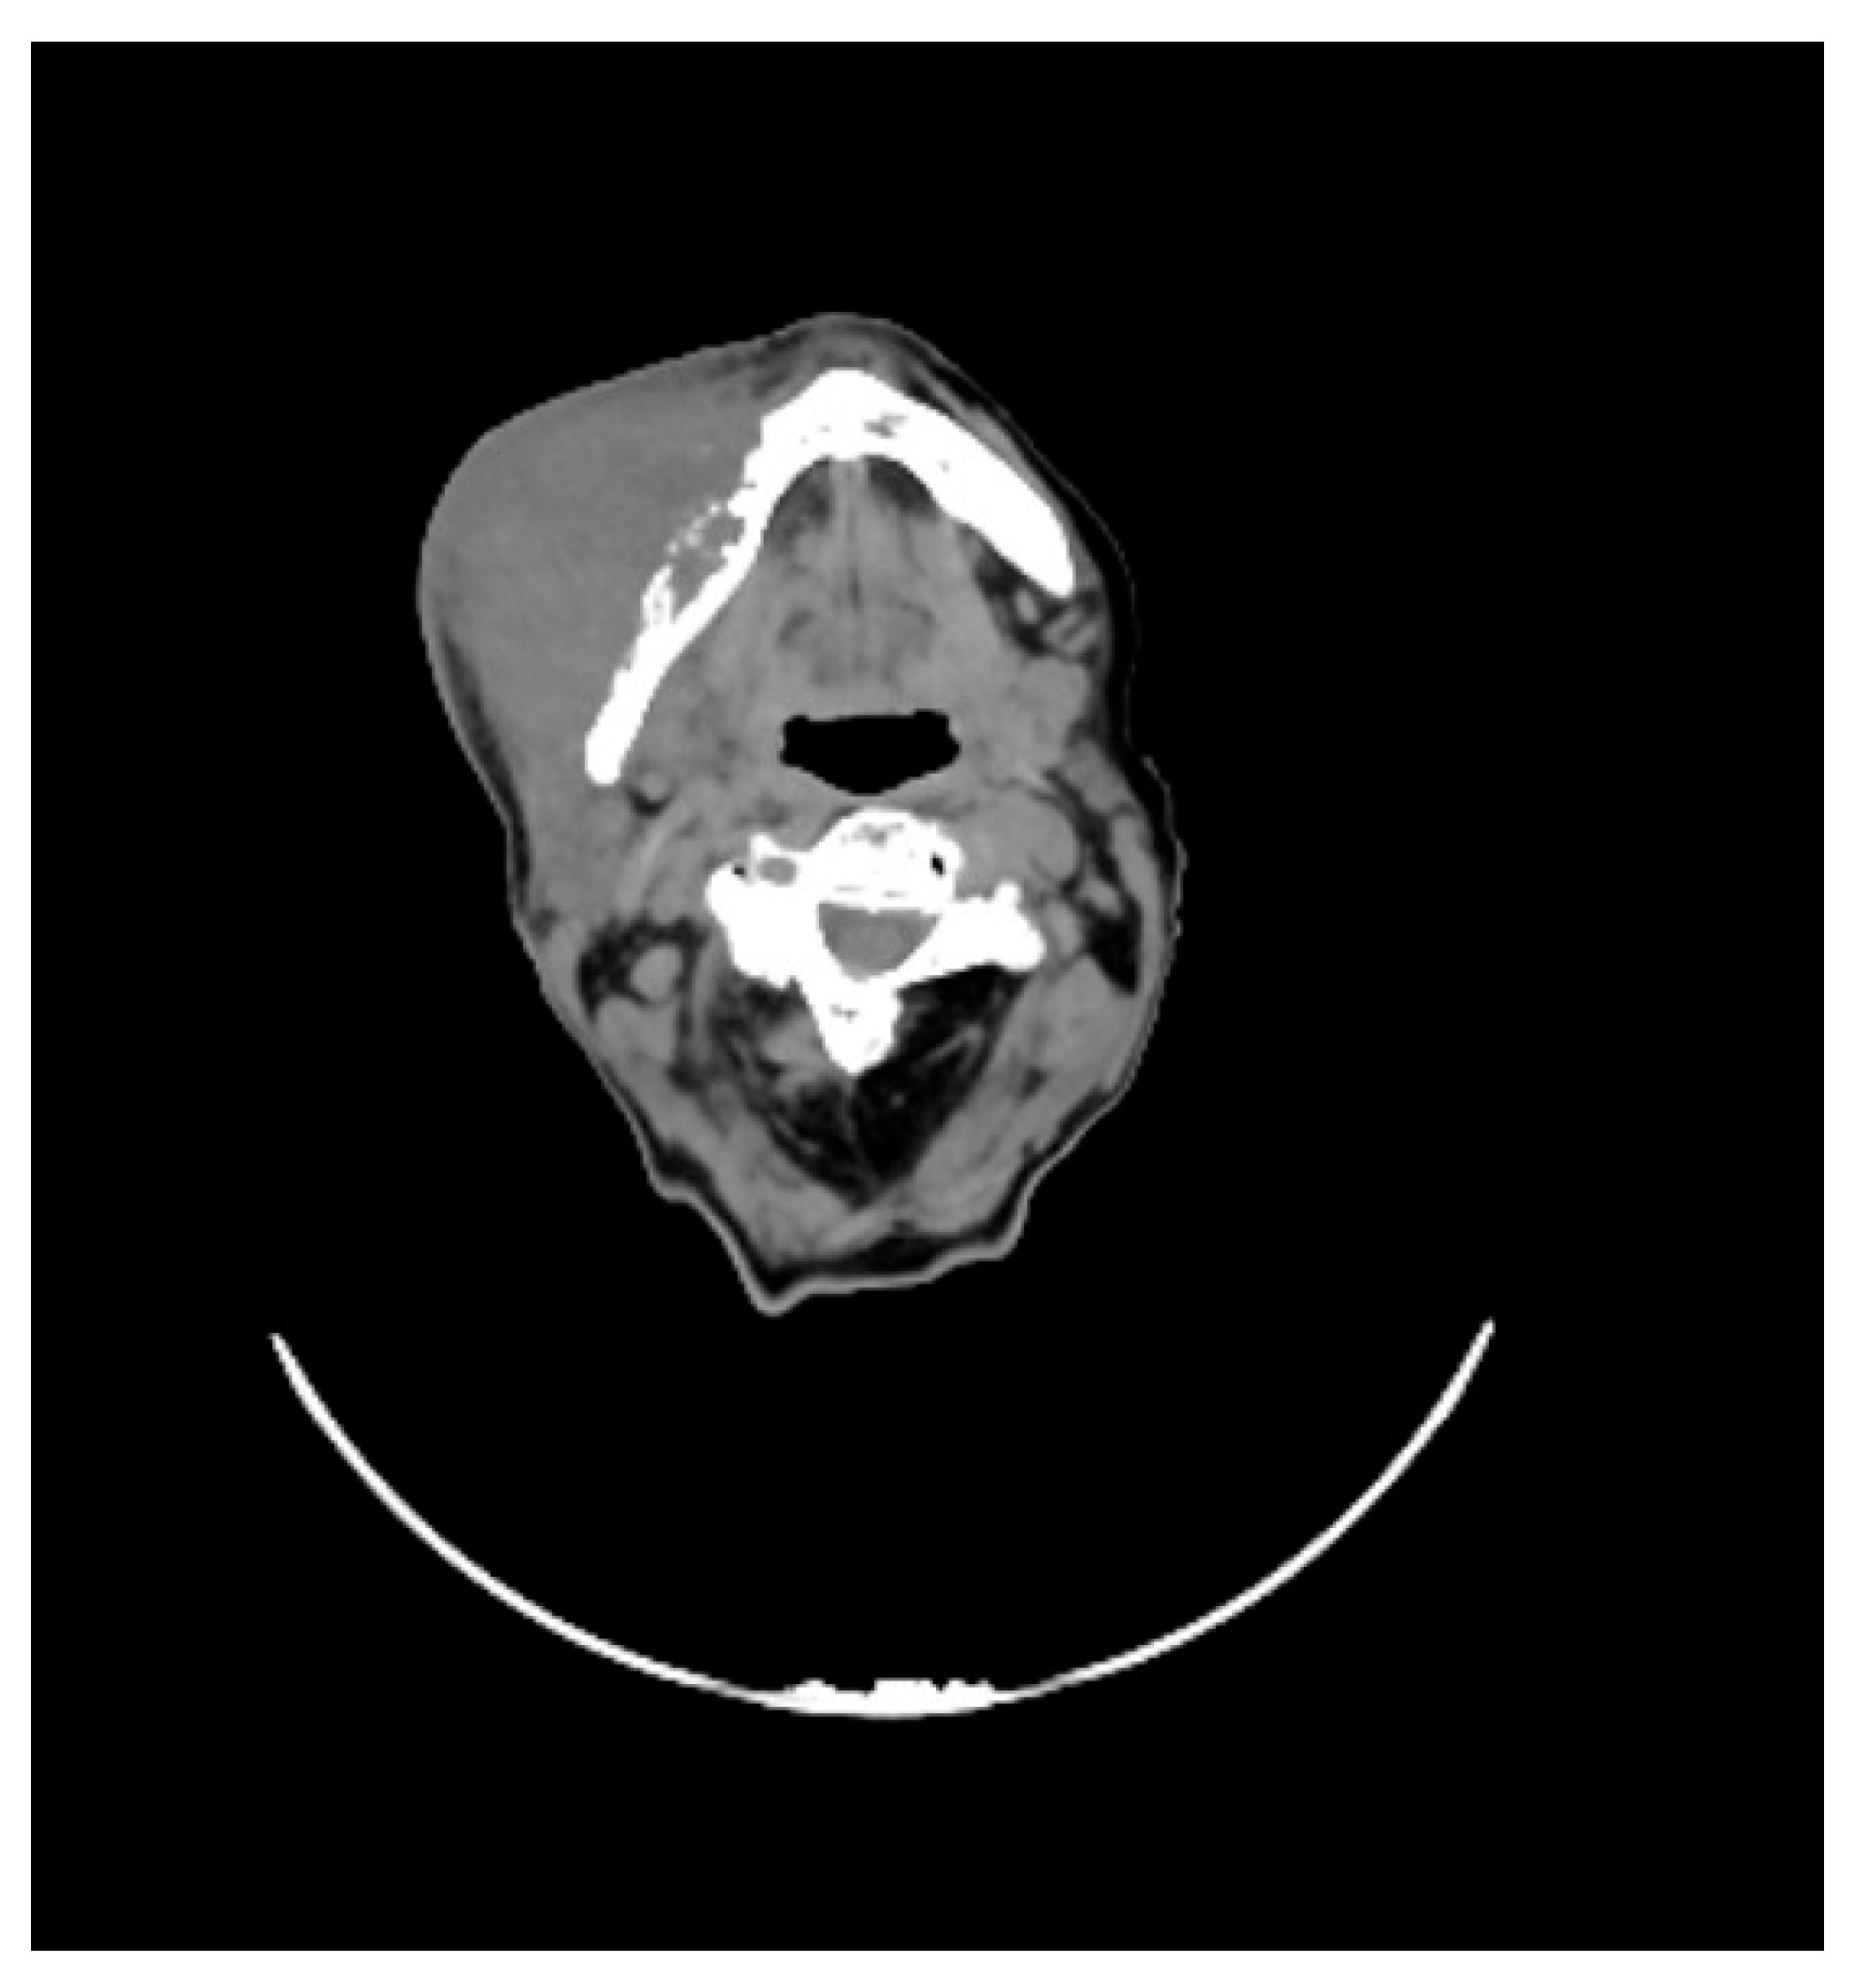

She underwent maxillofacial computed tomography (CT) scan, which revealed a lesion of the right genial mucosa with infiltration of the skin, buccinator muscle, and the cortex of the mandibular bone, affecting the alveolar canal, other than the presence of necrotic, colliquative, and confluent lymphadenopathies (Figure 1).

Figure 1. CT performed before the start of therapy, showing the extent of disease with infiltration of the skin and mandible.